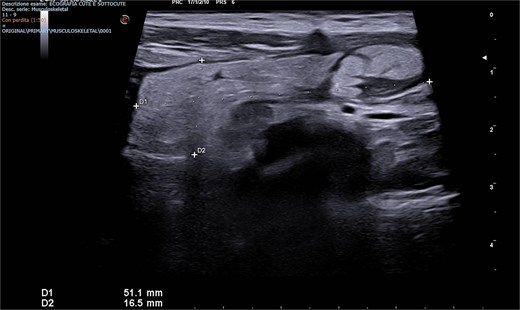

A scrotal ultrasound revealed a grossly hyperechoic area within the right inguinal canal measuring 50 × 20 mm associated with fine vascular spots on Doppler imaging, initially interpreted as thickened omental adipose tissue. No significant changes were observed during Valsalva maneuver, raising suspicion for an incarcerated omental hernia (Figs 1 and 2).

Emergency Department ultrasound images showing a hyperechoic mass occupying the right inguinal canal.

Emergency Department ultrasound images showing a hyperechoic mass occupying the right inguinal canal, with fine vascular signals on color Doppler. The lesion exhibited no change during the Valsalva maneuver and was initially suspected to be an incarcerated omental hernia.